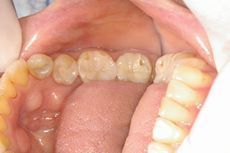

患者さんは20代の独身女性、確か病院の受付をされていた方です。上の写真は術前としていますが正確には術中です。上の歯の中央から向かって左側(患者さんにとっては右)の3本は実は仮歯が入っています。本当の術前は上の歯の中央から向かって右側(患者さんにとっては左)3本と同じような感じで歯ぐきとの境の所がまったく合っていない歯が入っていました。治療の必要があって向かって左側(患者さんにとっては右)を仮歯に変えたところ、慌てて来院され、「左側3本(向かって右側)も一刻も早くはずして入れ替えて下さい。これでは人に会えません。最終的にはいいものでいいですから 、とにかく仮歯だけでも急いで下さい。」と言われまして、「あなたは何年もこの歯を入れていたのですよ」とつっこみたくなりましたが、「それならばこの時点での写真を撮っておいて、最終的なものと比べてみましょう」ということで、写真撮影となりました。

(術前)

審美歯科術前.jpg